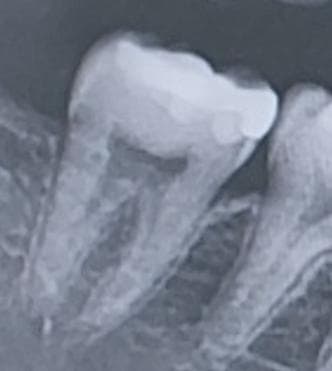

사진 47번에 위치한 어금니쪽 인레이를 한 부위가 옛날 중학교 시절 쯤 했던 인레이입니다. (현재 25살) 그렇다보니 시간이 경과해서 틈이 생겨 충치가 진행된 것처럼 보이는데 현재 증상으로는 해당 부위에 차가운물이 닿게 되었을 시 정말 미미하게 시린 경험을 겪고 있습니다. 하지만 지금 의문이 드는 점이 제가 치간칫솔을 최근에서 들어가는 공간이 되었는 것을 확인하고 치간칫솔을 무리하게 사용한건지 그것 때문에 시리게 된건지도 모르겠습니다.

사진으로는 충치여부를 정확하게 확인하기는 어려워 보입니다.

인레이 하방 이차충치가 의심되긴하나 신경에 근접하지 않았고, 치주인대 상태도 괜찮아보입니다 신경치료가 필요하진 않을 것 같고 다시 인레이 해주면 될 것 같습니다

충치를 제거해봐야 알겟지만 충치가 깊이 진행된것처럼 보이진 않아서 다시 인레이 치료를 하셔도 될것같습니다.